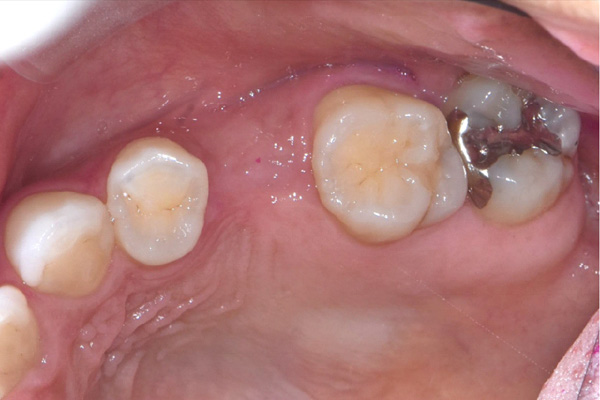

| 年代・性別 | 50代 男性 |

|---|---|

| 主訴 | 右下の歯がないのでインプラントをして欲しい |

| 治療期間 | 約6ヶ月 |

| 費用 | 600,000円 |

| 治療内容 | インプラント、骨造成、結合組織移植、セラミック修復 |

| 治療に伴うリスク | インプラント周囲炎 セラミックの破折、脱離 |